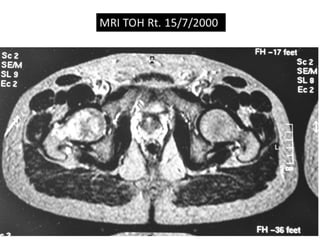

The document presents a detailed case study of a patient with transient osteoporosis of the hip (TOH) and spontaneous osteonecrosis of the knee (SONK) treated at Choithram Hospital & Research Centre in India. Over 20 years, the patient experienced multiple episodes of TOH and SONK with no history of trauma or co-morbidities, resulting in resolutions and recurrences of conditions. The information is intended for orthopedic surgery students and highlights personal experiences and case collections, with a disclaimer regarding content usage and potential controversies.